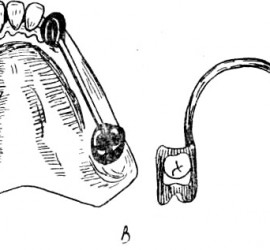

Опорными частями являются кламмеры или замковые соединения, телом — седловидный базис с искусственными зубами. Жевательное давление, падающее на тело съемного мостовидного протеза, передается так же, как и в несъемном, на опорные зубы. Ткани, лежащие под телом протеза, не испытывают непосредственно жевательного давления. Большим преимуществом съемных мостовидных протезов является то, что одним протезом можно соединить различные группы зубов, например, жевательные с обеих сторон или фронтальные и жевательные. Соединение зубов правой и левой сторон челюсти или зубов, различно функционально ориентированных в одну систему, позволяет укрепить зубы с пораженным пародонтом. Кроме того, расширяются возможности применения мостовидных протезов.